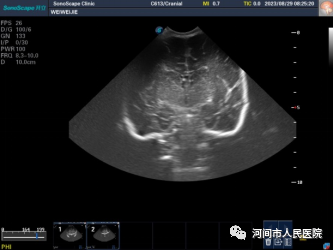

▲新生兒(er) 缺血缺氧性腦病